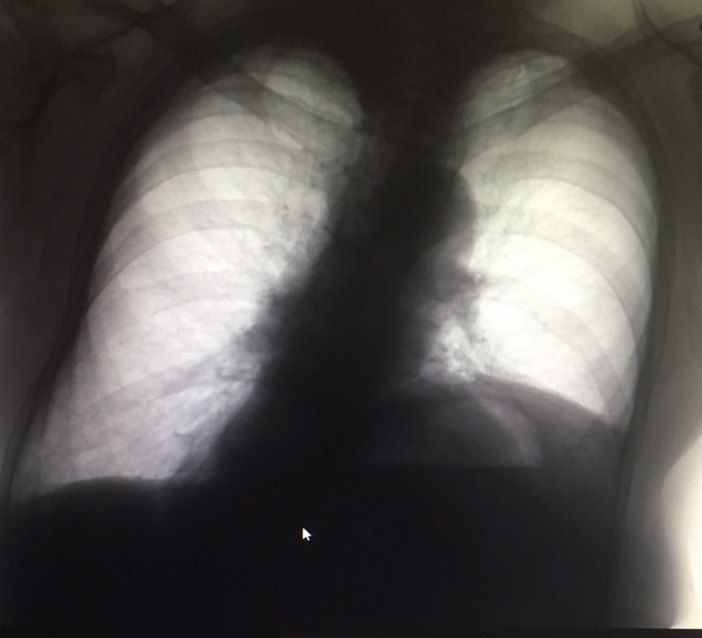

Подскажите,это перелом справа?женщина 1949г.р

Перелом седалищной кости справа?

Боковой сделали. Подскажите как описать

В таких ситуациях очень учёные травматологи говорят что это старый перелом

В таких ситуациях очень учёные травматологи говорят что это старый перелом